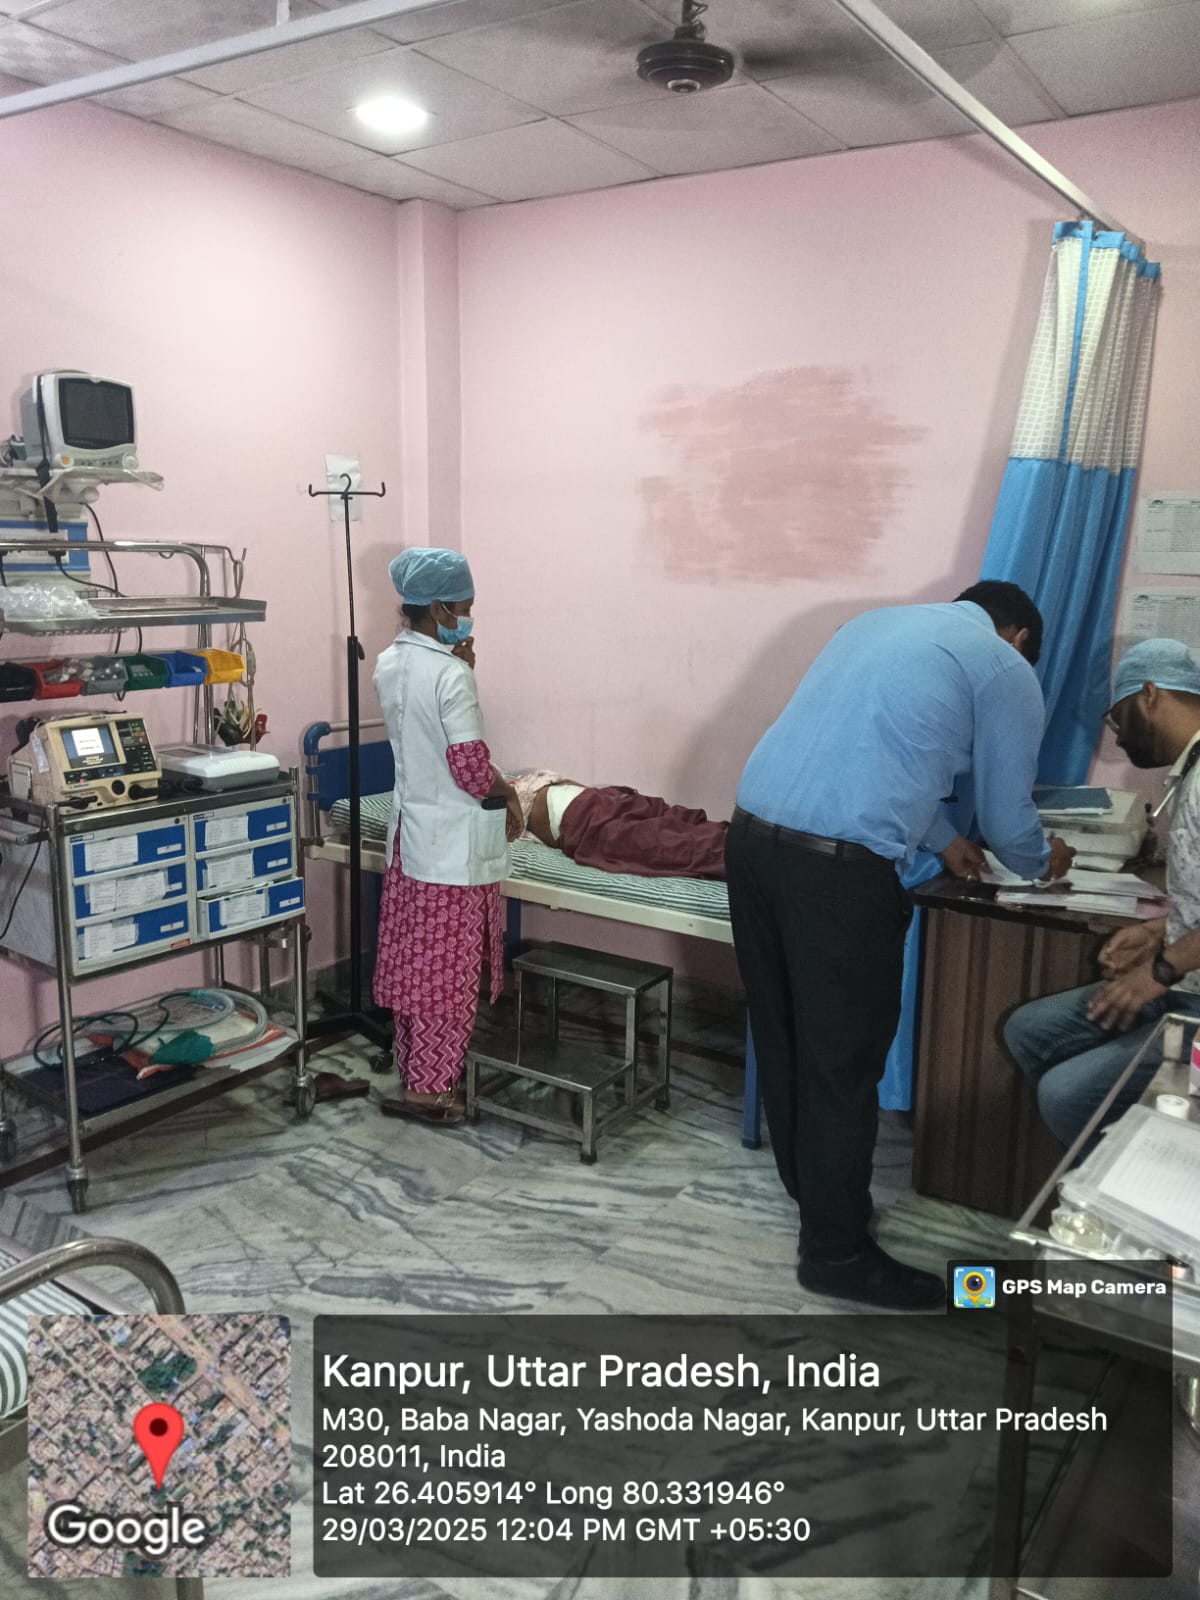

See Our Work!

Here’s a quick look at the beauty transformations that we have worked on. Whether it is a

temporary makeup or a complete makeover, you can trust us.